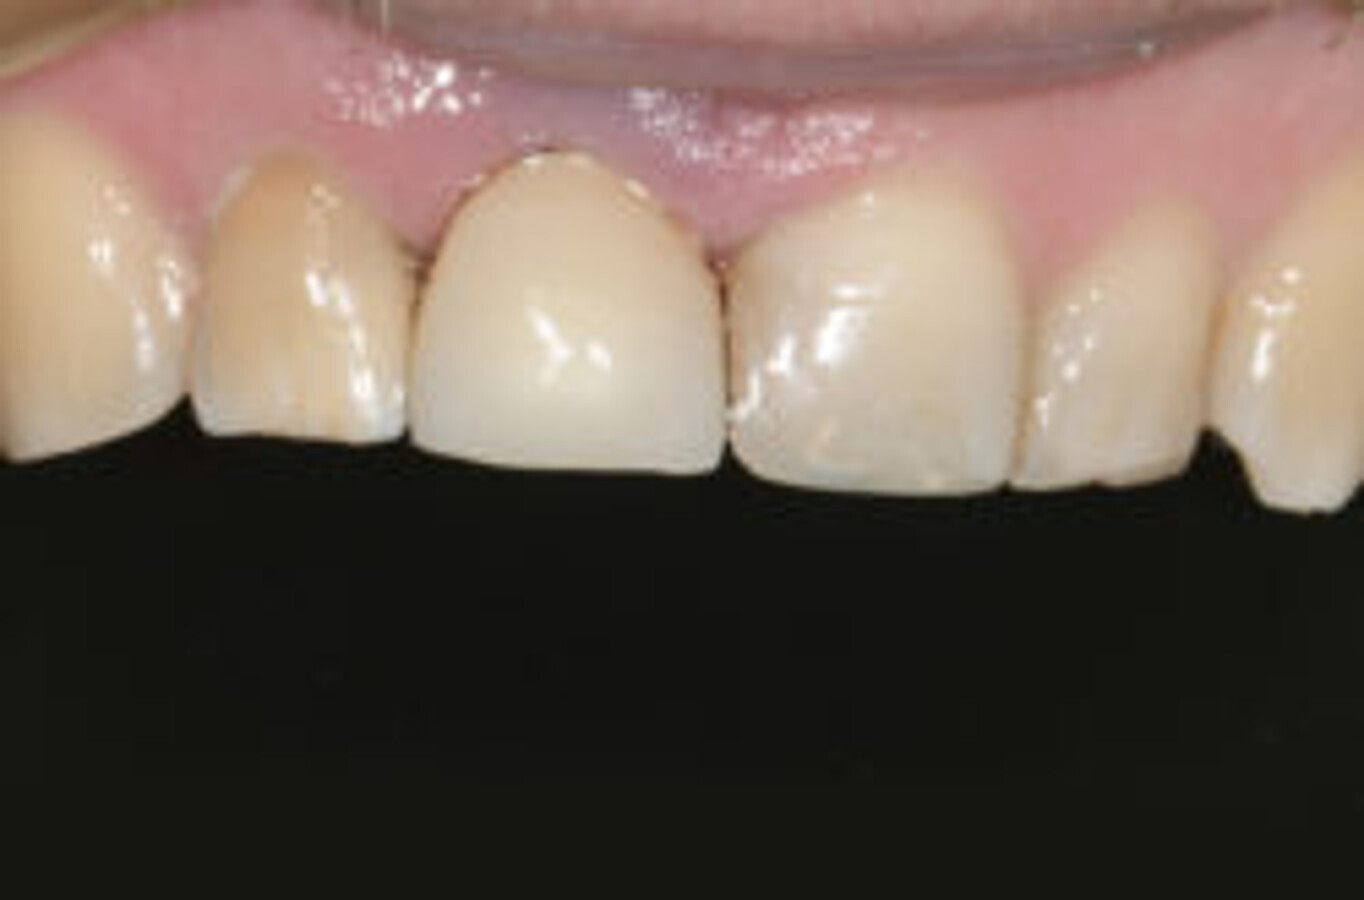

图16. Ankyos种植体的牙床下植入。将螺丝固位的IPSe.max牙冠安装在Atlantis基台上(无功能修复)。

图18. 种植体周围的软组织适应良好。此外,在#12(根管治疗后)安装了陶瓷冠,#21和#22安装了陶瓷贴面。三年的随访显示软、硬组织无殊。

使用simplant guide,精准、安全地行骨下种植(图12-15)。Atlantic 基台上的螺丝固定全瓷冠(非功能性修复)在种植后即被安装(图16)。后续CBCT显示,simplant软件完美定位了种植体(图17)。

治疗非常成功,最终结果患者十分满意。三年后复诊可见种植体周软组织适应性良好(图18)。此外,#12根管治疗后安装了陶瓷冠,#21和#22安装了陶瓷贴面。